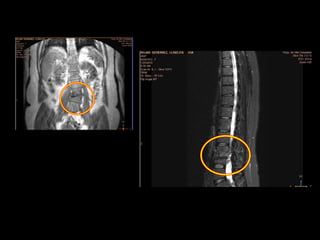

IMAGEN RESONANCIA MAGNETICA

25-01-16: Pinzamiento severo derecho del espacio

intervertebral L4 lo que condiciona escoliosis de

concavidad derecha y estenosis del agujero

foraminal L3-L4 derecho de aspecto secuelar no

activo.

Pinzamientos facetarios L4-L5 bilateral y L3-L4

izquierdo correlacionar con datos clínicos.